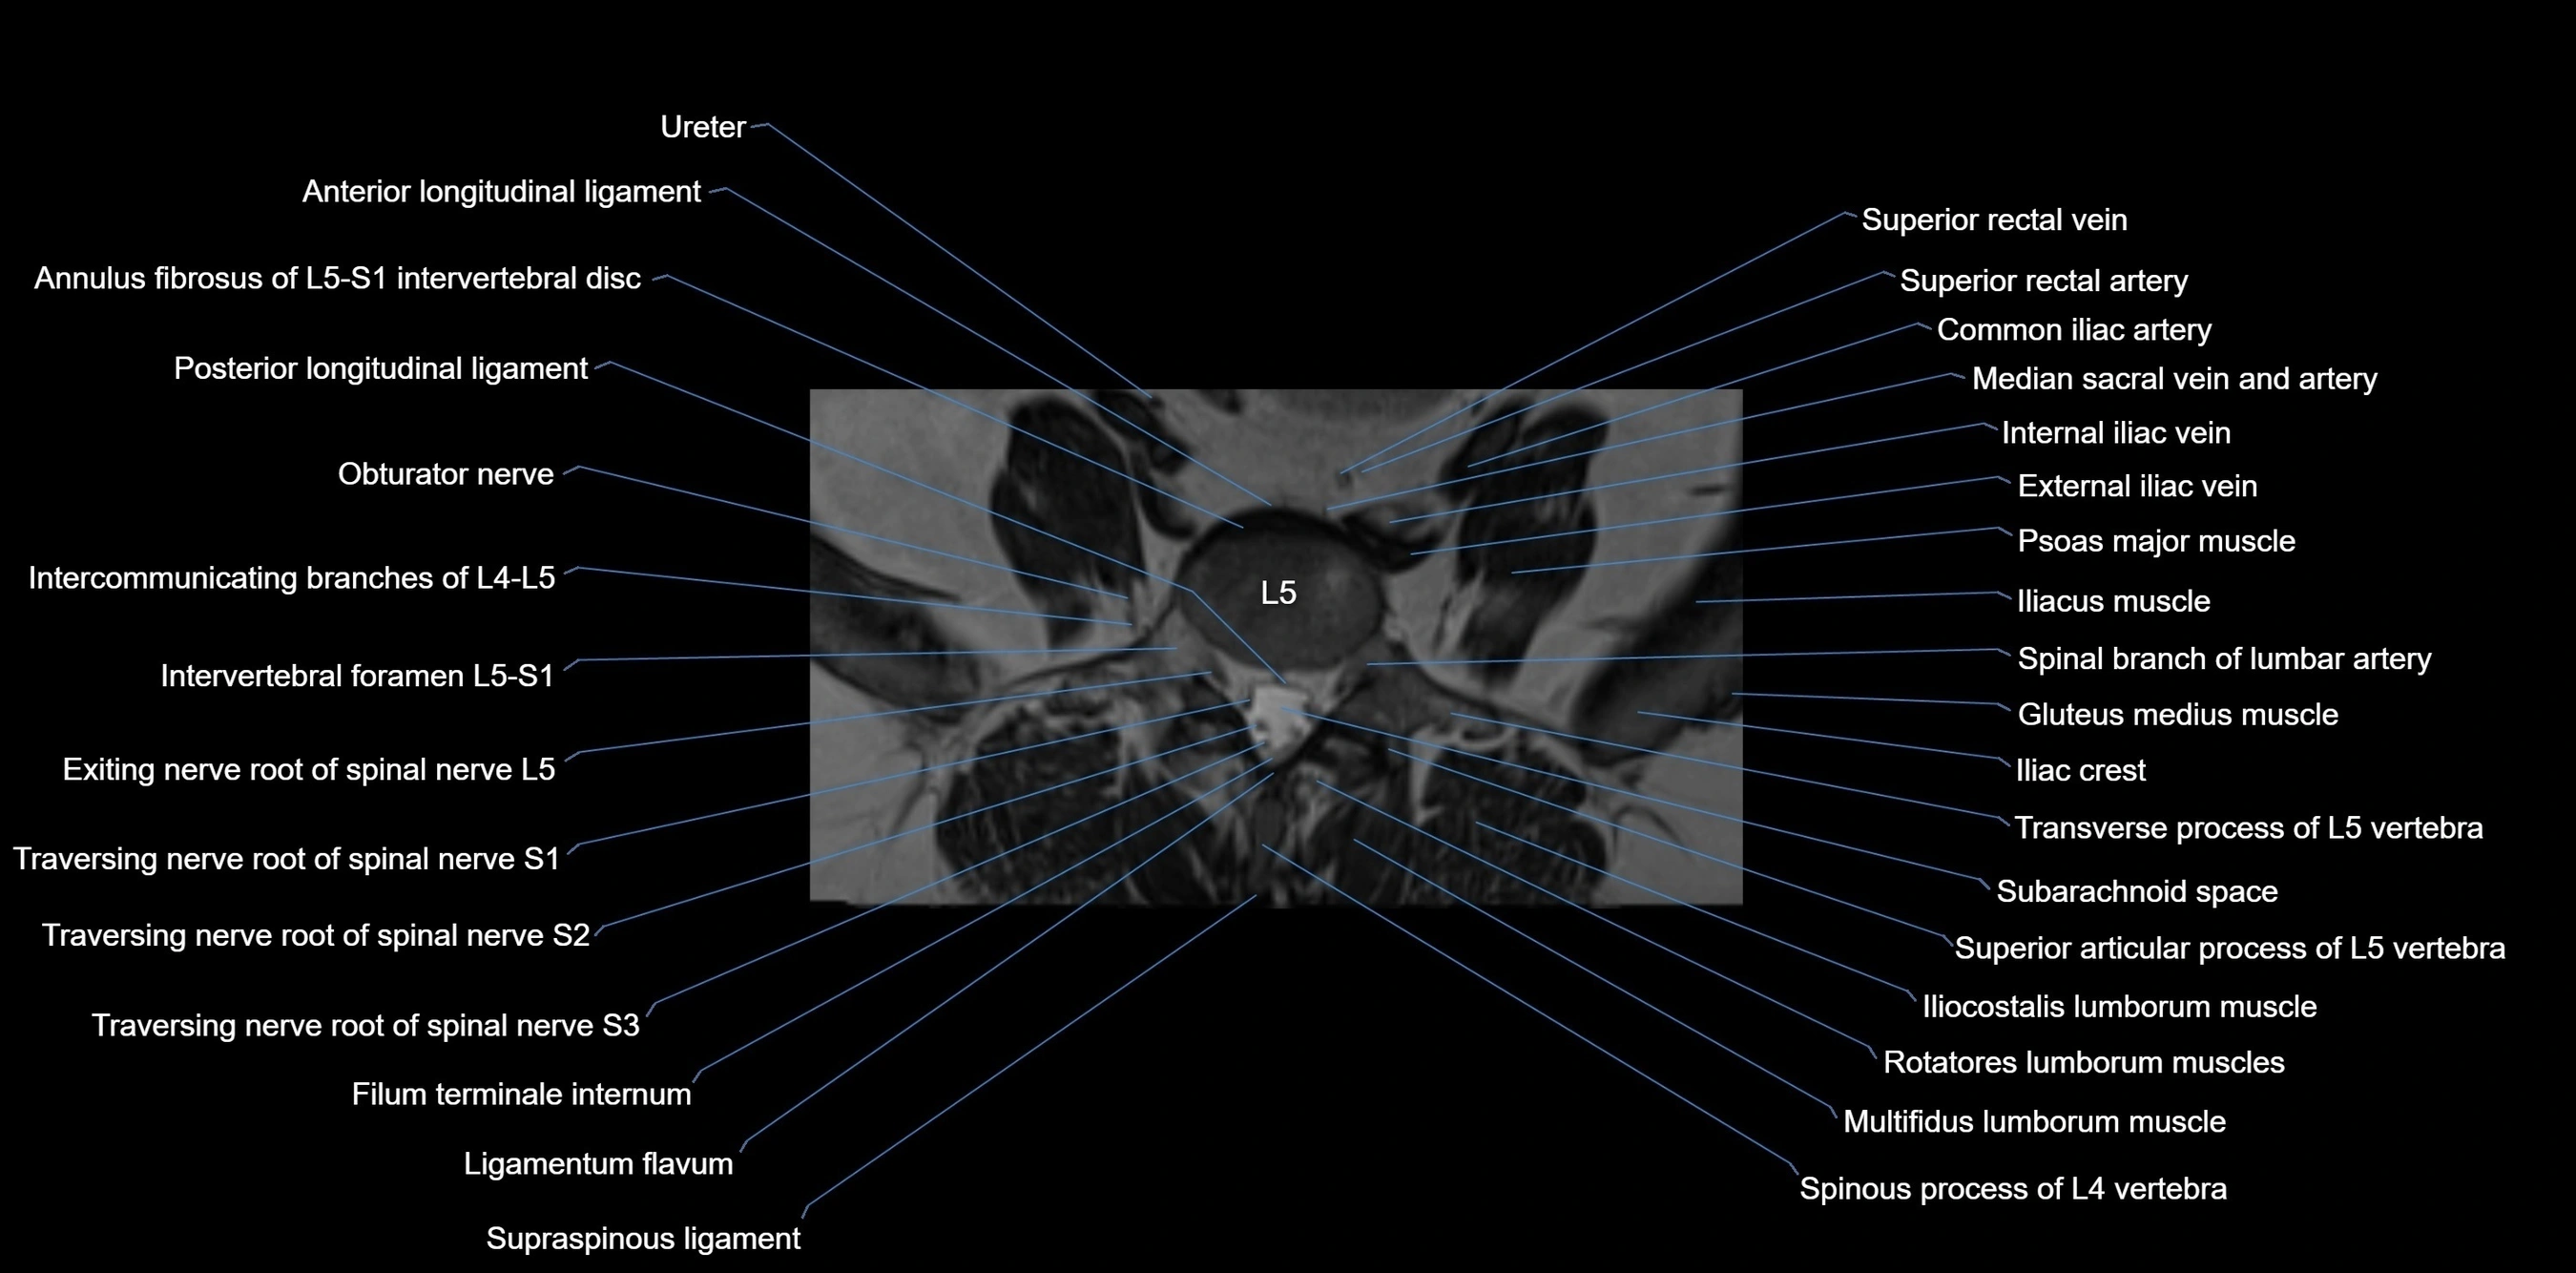

MRI image

image